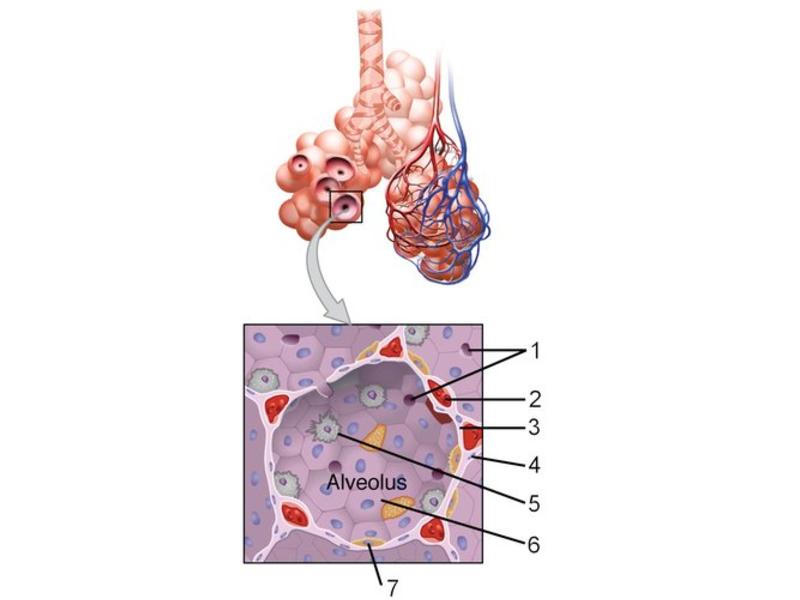

Components of the Blood-Air Barrier?

- Alveoli